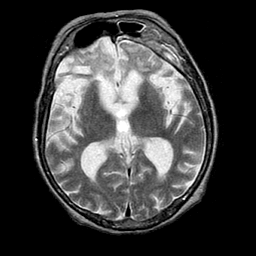

Pick's Disease, MR Study mr-t2 -- Slice #11

[Home][Help][Clinical] Slice 11